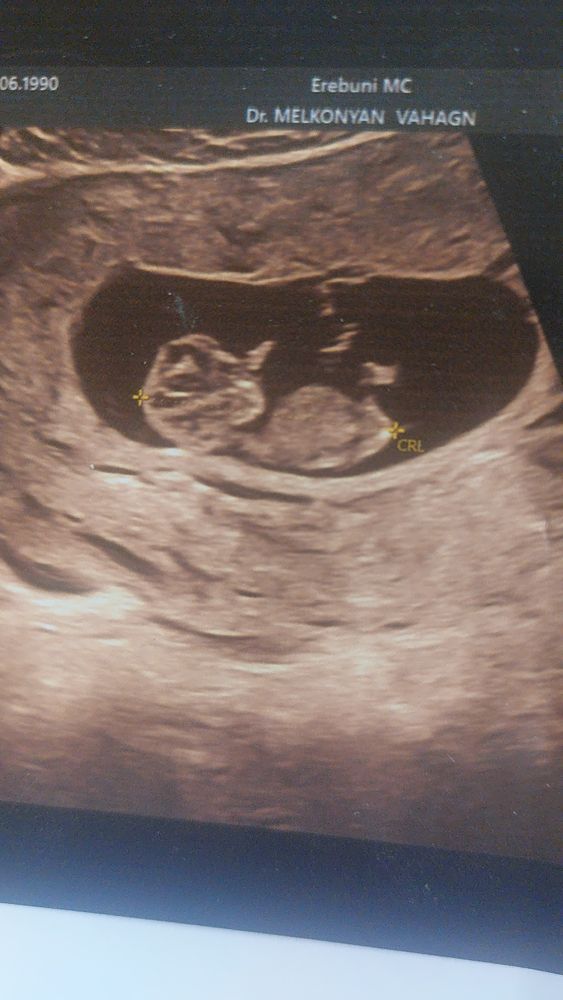

Узи 13 недель

Если на первом фото вот то, что торчит вверх - это половой бугорок, то мальчик:)

Я вижу девочку, но это не 100%, так как ракурс не очень удобный для меня

Ракурс не тот, не видно. Остаётся гадать🤗🌷🌷🌷

Людмила, на скриниге сказали мальчик☺️ но после моих девченок я в такое не верю😄

Anna Сагумян, ой, первое фото не увидела 🙏 там на девочку больше похоже, но врачу виднее. Пусть будет мальчик🤗Если бы мне сказали, что у меня девочка, я бы тоже не поверила😄

По этому фото сложно сказать. Но я предположу мальчика. Но это больше пальцем в небо